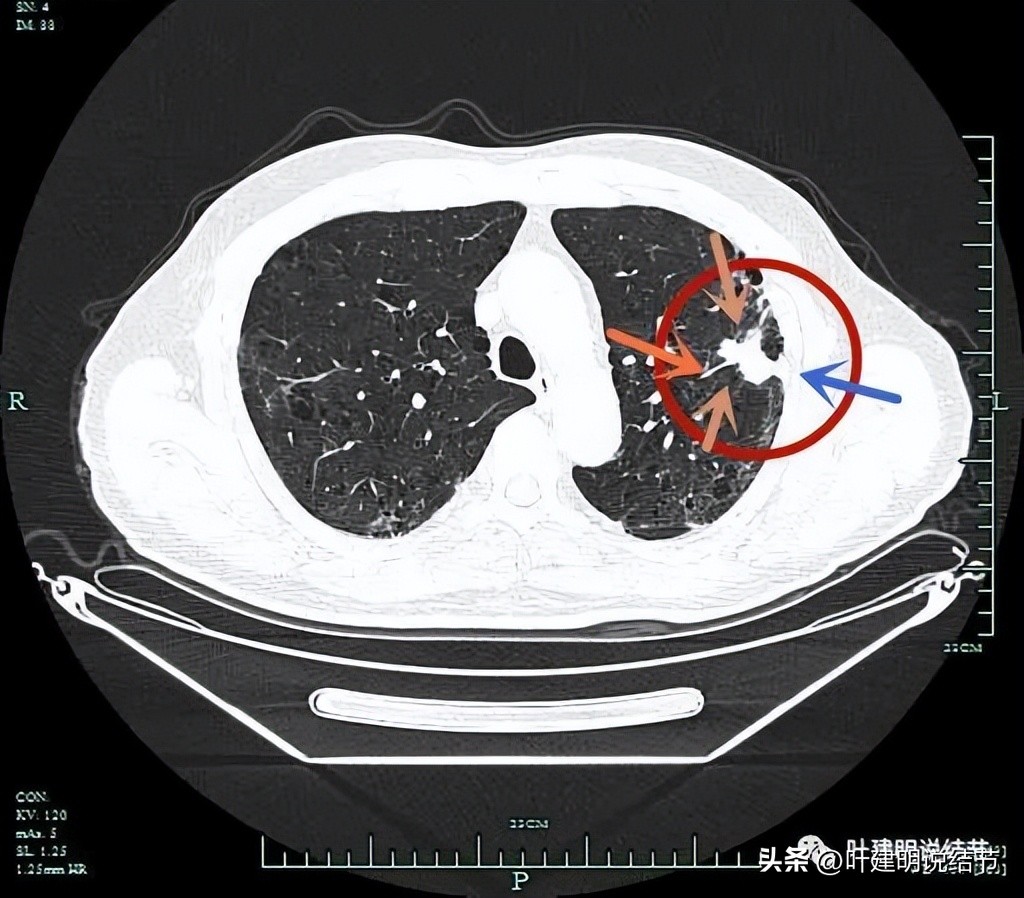

左上病灶开始出现,周围伴慢性炎的表现(红色圈起来部位);其他余部分有多处炎性改变(粉色圈起来的)。

分叶征(砖色箭头);毛刺征(紫色箭头);胸膜牵拉(蓝色箭头);病灶有膨胀感(红色箭头)。

上图层面明显明显的收缩力、分叶、胸膜牵拉以及血管进入(桔色箭头)。